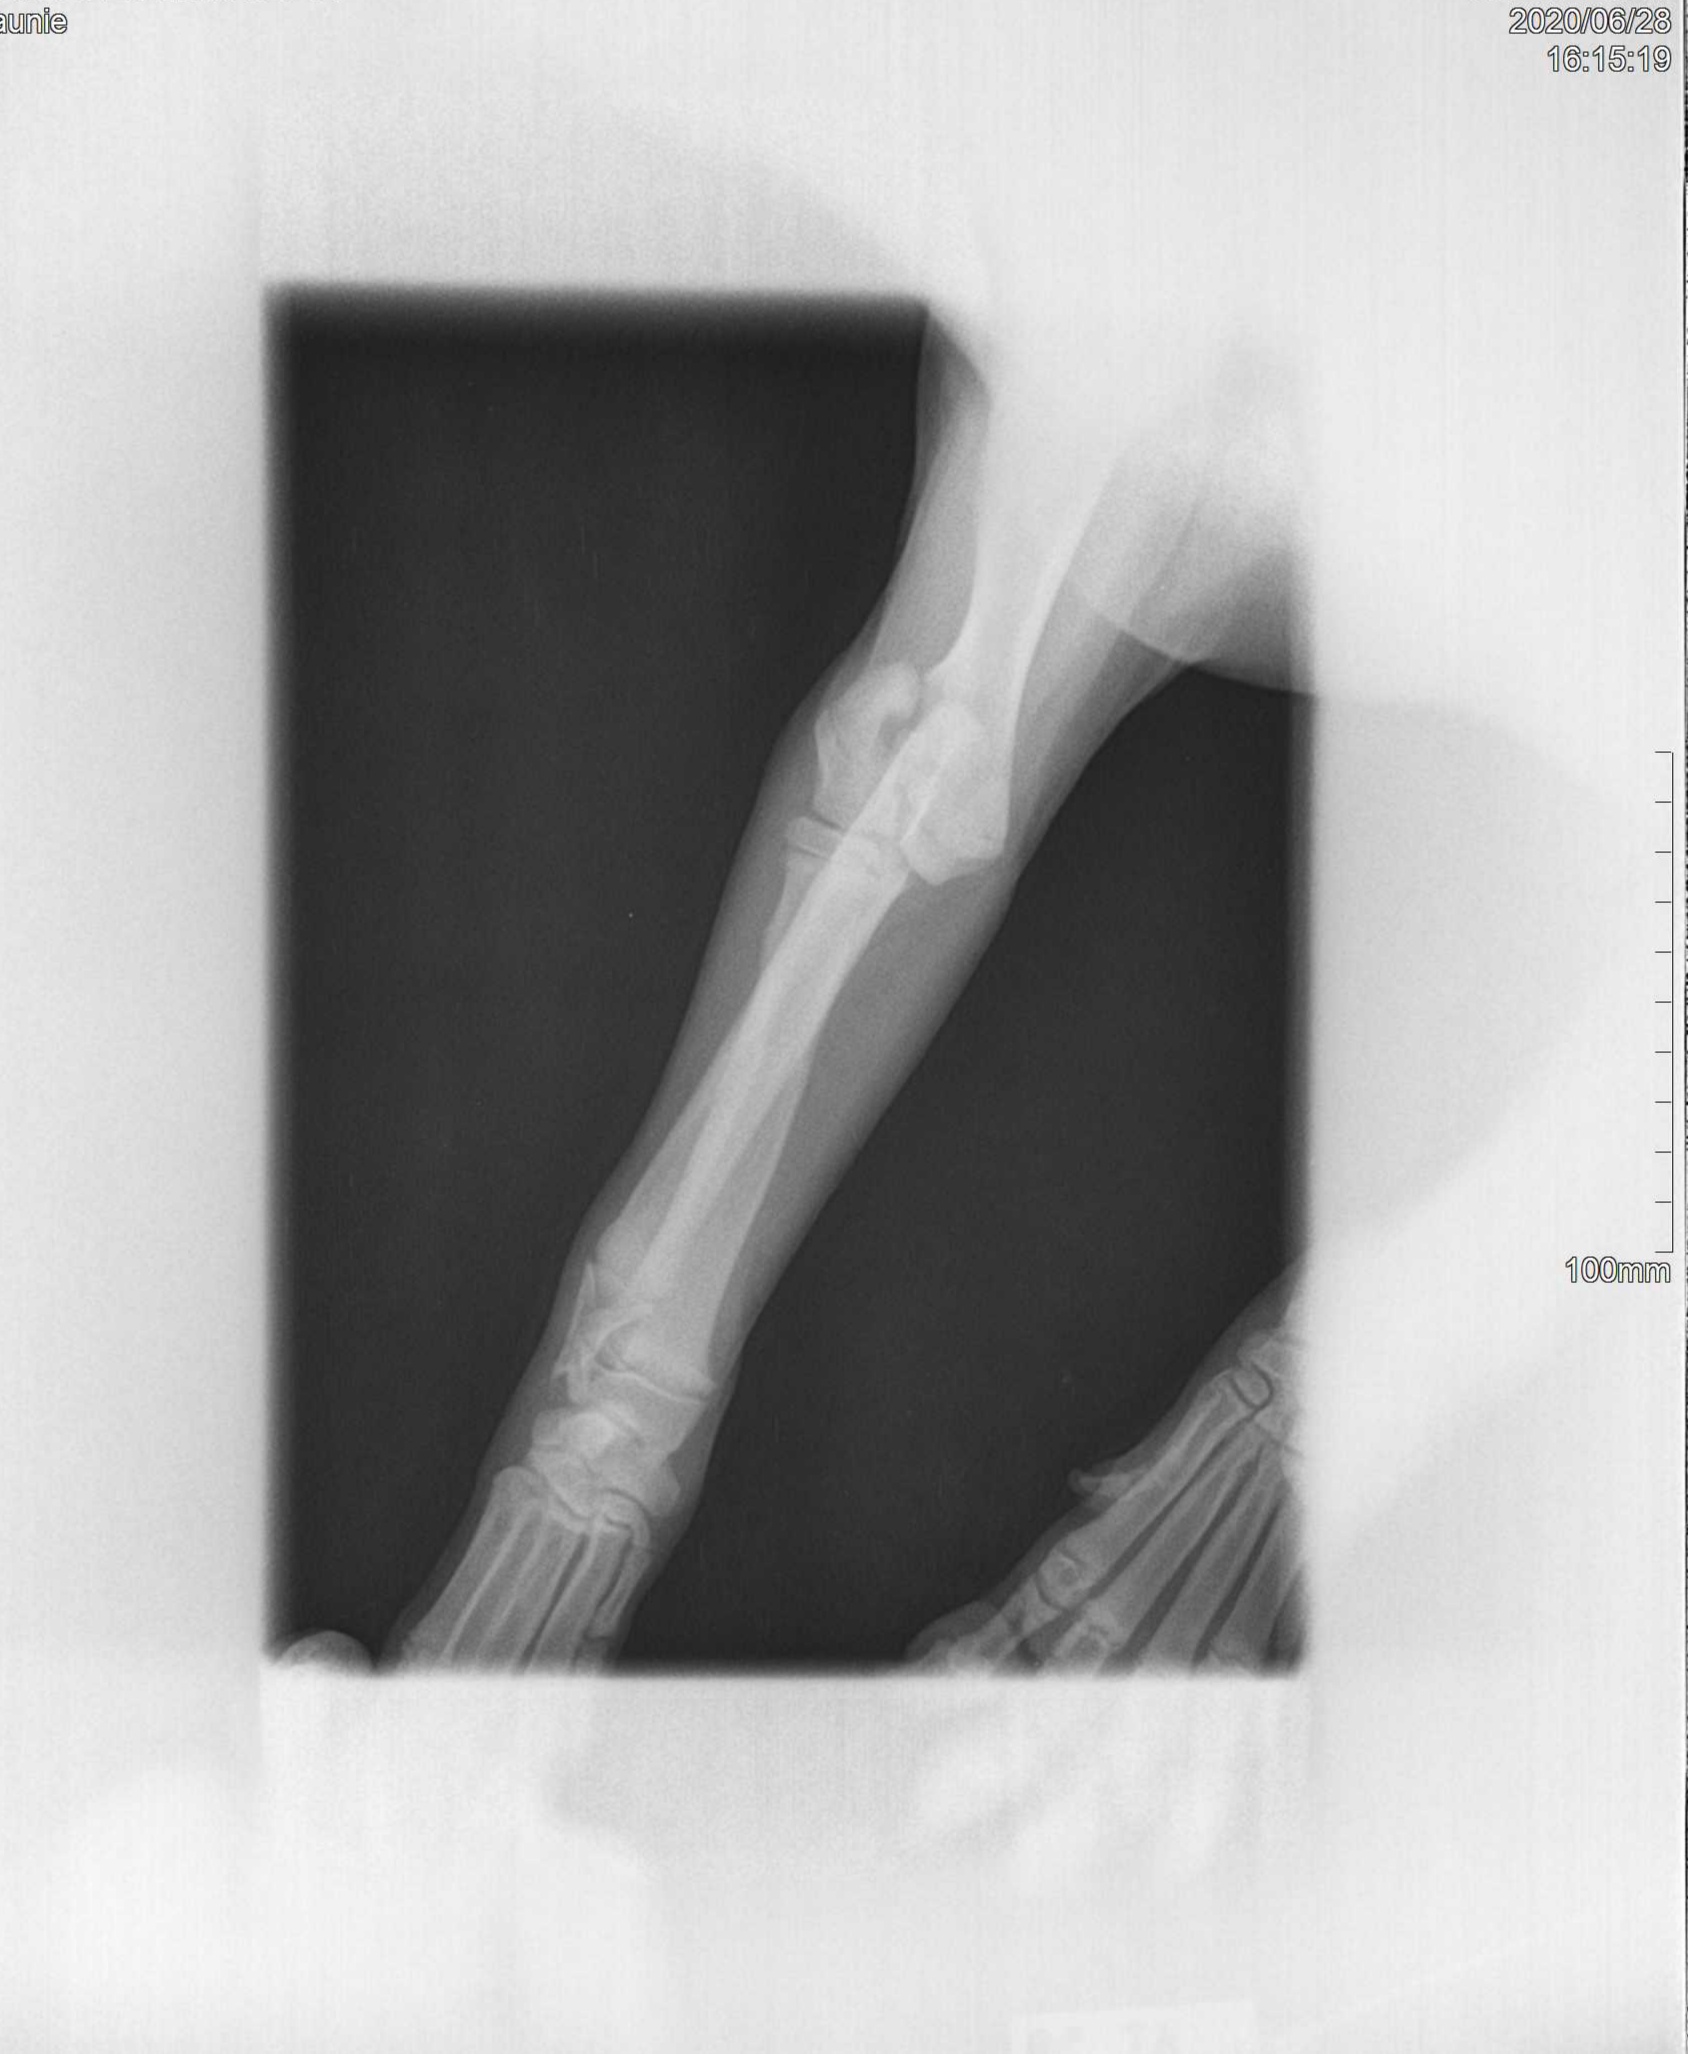

Dobrý den, Chci se zeptat a mít k porovnání další názor. Naše fenka labradora ( 4 měsíce) měla úraz pádem ze schodů. Na veterině mi řekli, že je tam fraktura v oblasti lokte a je nutná operace. Na druhý den byla provedena. Řekli mi, že loket spravili za pomoci silikonového vlákna a s prášky nás poslali domů. Teď je to 13.den od operace, vyndali nám stehy a řekli že noha je trochu vyrotovaná, ale pohyblivá. Že by se to mohlo srovnat až začne nohu používat a že můžeme začít s rehabilitační. Ideálně s plaváním. Fenka nohu vůbec nezatěžuje. Neustále ji má mírně pokrčenou, nepropíná ji a loket má o poznání větší než ten druhý i více od těla. Mám strach, že zůstane s následky do života, nebo že operace měla proběhnout jiným způsobem. Použít například nějaké šrouby. Má otázka zní.. Jak by jste postupovali vy? Zdá se vám postup správný? Co se s tím dá dělat v této fázi? Je možná případná reoperace? Jaké nám hrozí případné následky? Přikládám foto rtg. Předem děkuji za odpověď